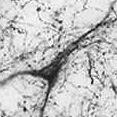

SERTThis mouse monoclonal antibody displays punctate staining along fibers in regional patterns consistent with 5-HT fibers. Neurons are detected in the Dorsal/Median Raphe Nucleus